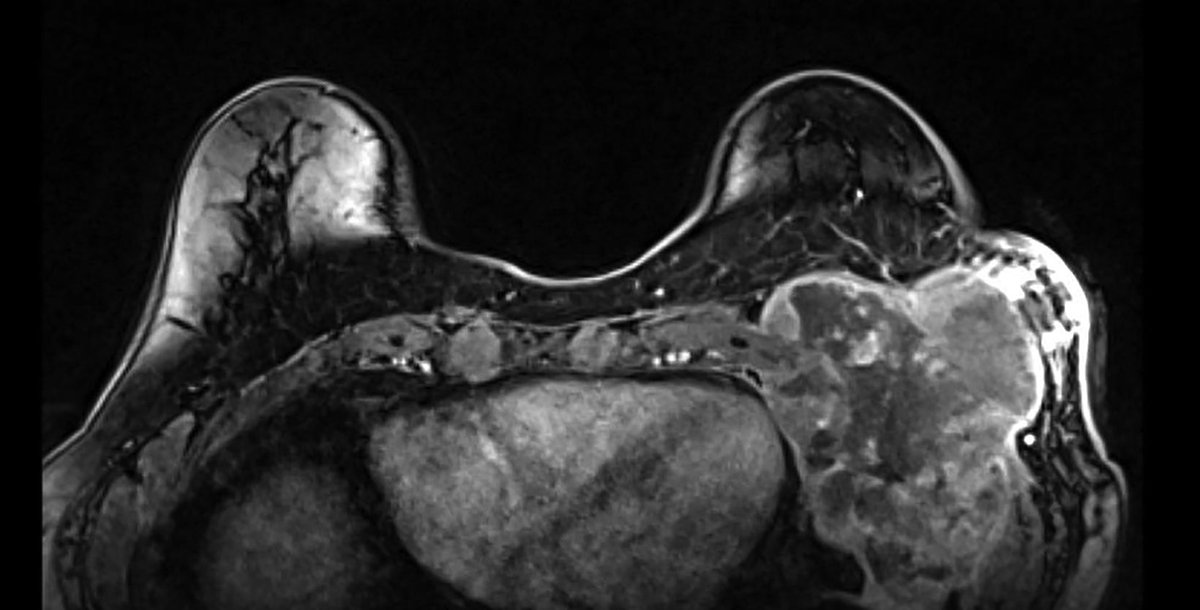

Case Study: Radiation Therapy-Induced Toxicity in a Breast Cancer Patient With Variance of Unknown Significance in the Ataxia Telangiectasia Gene 🔗 ow.ly/kZN750XaMkC ⚠️ The following content contains medical images that may be disturbing to some viewers. Viewer…

Applied_RadOnc's tweet image. Case Study: Radiation Therapy-Induced Toxicity in a Breast Cancer Patient With Variance of Unknown Significance in the Ataxia Telangiectasia Gene

Case Report: Radiation Recall Dermatitis with Docetaxel and Cyclophosphamide in a Case of Early Stage Breast Cancer Considered High Risk 🔗 ow.ly/TALj50XawBh ⚠️ The following content contains medical images that may be disturbing to some viewers. Viewer discretion is…

Applied_RadOnc's tweet image. Case Report: Radiation Recall Dermatitis with Docetaxel and Cyclophosphamide in a Case of Early Stage Breast Cancer Considered High Risk